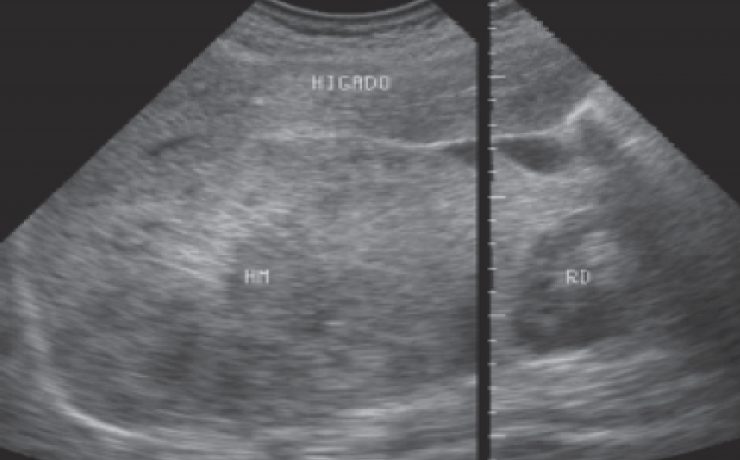

Carcinoma de vías biliares. Tumor de klatskin

Las estenosis malignas que involucran los conductos biliares pueden ser: Primarias ó propias de los conductos y canalículos biliares. Secundarias o por extensión desde otros órganos como el hígado, la vesícula, el páncreas, el duodeno ó ganglios linfáticos adyacentes. Ubicación Tercio superior: desde la confluencia hasta el hepático común Tercio